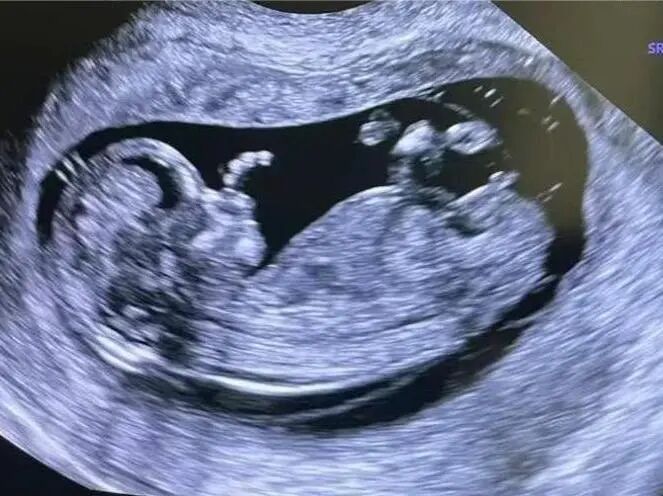

您是否也遇到过这些尴尬时刻?提重物时突然漏尿、运动时总觉下腹坠胀、更年期后总想跑厕所......这些信号可能在提醒:盆底肌需要关爱了。 盆底肌群如同"弹簧床",承托着膀胱、子宫等器官。妊娠分娩、雌激素变化、长期腹压增加等因素,都可能导致这张"网"松弛。若不及时干预,可能发展为: ▷ 盆腔器官脱垂(子宫/阴道膨出) ▷ 压力性尿失禁(咳嗽/大笑漏尿) ▷ 排便障碍(便秘/失禁) ▷ 性生活质量下降 【哪些人需要关注盆底筛查?】 ✓ 产后42天妈妈(尤其经阴道分娩) ✓ 频繁漏尿或排尿困难 ✓ 长期便秘/慢性咳嗽 ✓ 更年期女性 ✓ 性生活疼痛或下腹坠胀人群 【无创筛查新选择:盆底超声】 不同于传统指检,这项技术通过会阴体表扫描: ⏩ 多维度观察静息/收缩/用力状态 ⏩ 精准评估肌群损伤程度 ⏩ 动态捕捉器官位移情况 女性盆底三维多层显像 【检查须知】 ✔️ 避开经期 ✔️ 检查前排空膀胱 ✔️ 穿宽松裤装更方便 ✔️ 配合医生指令做缩肛/屏气动作 盆底超声检查 女性健康管理不该止于体检常规项。建议存在相关症状的女性,及时到正规医院妇产科或超声科咨询。早筛查、早干预,让盆底肌恢复应有的"托举力"。 注:部分图片来源于网络,如有侵权,请联系删除。 贵州航天医院超声科专家团队 吴艳辉 中共党员,超声科学科带头人、主任,主任医师 专业擅长:从事超声诊断工作约30年,对心血管、小器官超声、超声引导下介入等具有丰富的临床经验。 胡大海 超声科副主任,副主任医师 专业擅长:从事超声工作17年,对心血管、外周血管、浅表器官超声诊断等具有丰富的临床经验。 骆科美 中共党员,超声科副主任医师 专业擅长:从事超声诊断工作33年,对胎儿心脏及颅脑、妇产超声诊断、盆底超声等诊断具有丰富的临床经验。 刘 敏 超声科副主任医师 专业擅长:从事超声诊断工作20余年,对妇产科超声、心脏血管超声诊断具有丰富的临床经验。 贵州航天医院超声科简介 基本情况 贵州航天医院超声科配备多种超声检查设备(飞利浦彩超(IU-22、IU-Elite、HD11、Q5、Q7),迈瑞超声I9、DC-6、DC-8、GE-E8及床旁机,彩色超声诊断仪等),设有心血管诊室、妇产科诊室、腹部诊室、绿色通道、浅表小器官等检查室。 诊疗范围 科室业务覆盖腹部、泌尿、妇科、产科(常规、NT筛查、III级筛查超声检查及高危妊娠监护)、成人心脏、外周血管、浅表器官(包含甲状腺、乳腺、阴囊、眼睛等)、颅脑(小儿颅脑、成人颅脑)、小儿肺超、造影、盆底、腹直肌、肌骨神经等检查及各种介入引导。 专科特色 四肢血管超声检查、双胎产前筛查及超声监护、超声造影检查技术、介入超声临床应用、经颅脑实质超声辅助筛查诊断帕金森病、女性性早熟超声诊断、盆底超声检查等。 NT超声检查 超声介入引导 肝脏超声造影 甲状腺造影 颅脑超声帕金森辅助检查 乳腺超声造影 上肢动静脉造瘘超声检查 双胎超声筛查 下肢血管超声检查 右心造影 END